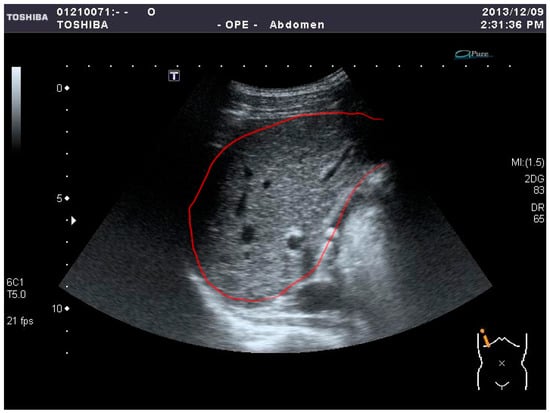

In this paper, three feature selection models—(i) sequential forward selection (SFS) [52,53], (ii) sequential backward selection (SBS) [53,54], and (iii) F-score [55]—are adopted to distinguish the two liver diseases. Marill and Green introduced a feature selection technique using the divergence distance as the criterion function and the SBS method as the search algorithm [52,53]. Whitney discussed its ‘bottom-up’ counterpart, known as SFS [53,54]. In this research, a large number of features are included, comprising 96 features from each sample. If all of them are used to train a classifier, it not only takes too much time but also cannot easily achieve high accuracy. To reduce the processing time and improve the accuracy, it is necessary to search for the important features from the feature set. Then, the crucial features of the samples are used to train and test by SVM. We took several steps to achieve this goal. First, in the ultrasound images, the liver lesions are marked by experienced physicians and the regions of interest (ROIs) are circled inside a red boundary, as illustrated in Figure 1, meaning that part of the liver lesion is located inside the red boundary of the whole-liver image. Second, all features are extracted from the collected ROIs. Third, several feature selection processes are carried out to optimize the feature set. Finally, the optimal feature sets are used to train and test by SVM.

In medical imaging, the protocol of Digital Imaging and Communications in Medicine (DICOM) [12] is the standard for the communication and management of medical imaging information; therefore, DICOM files are typically used. In this research, for the convenience of image analysis, the original US images, supported by the Medical University Hospital in Taipei, were stored and then converted into 256-grayscale BMP files by MATLAB for more convenient processing. The images were from 79 cases of liver diseases including 44 cases of HCC and 35 cases of liver abscess. First, the original images were marked by experienced clinicians and verified in clinical reality. Then, the 32 × 32-pixel ROIs were selected inside the marked boundaries, as presented in Figure 1. In Figure 2, the 32 × 32-pixel ROIs were sampled from the marked image. All samples were collected from the liver disease images for later procedures, as shown in Figure 3. In this research, we sampled 400 ROIs of each kind of disease for training and testing.

Figure 1. An example of the cropping process for the original US image.